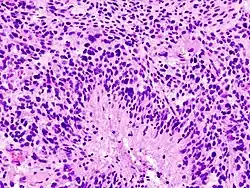

Patogênese

O glioblastoma surge no próprio cérebro, mais especificamente dos astrócitos, que são células responsáveis por algumas funções desta área nobre do ser humano. Quando um tumor tem sua origem definida pelos astrócitos, diz-se que é um astrocitoma. Um glioblastoma é um tipo de astrocitoma e seu grau de malignidade é o mais avançado (grau IV), ou seja, extremamente agressivo. É mais frequente em adultos entre os 35 e os 70 anos de idade, mas não é incomum ocorrer em outras idades.